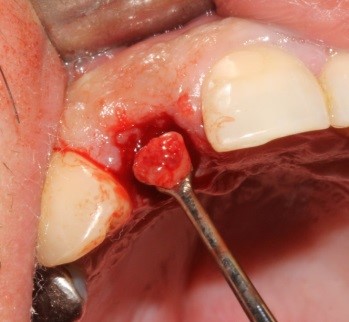

Se procedió a la remoción de la pieza dentaría fracturada, en forma totalmente atraumatica, la eliminación total de tejido de granulación, con hoja de bisturí nº 15 se realizó una incisión compensatoria con el fin de exponer la fenestracion ósea, colocación de matriz ósea bovina Ostium Max, en el defecto óseo, en la fenestracion con pérdida total, de la tabla vestibular del alveolo.

6

7

8